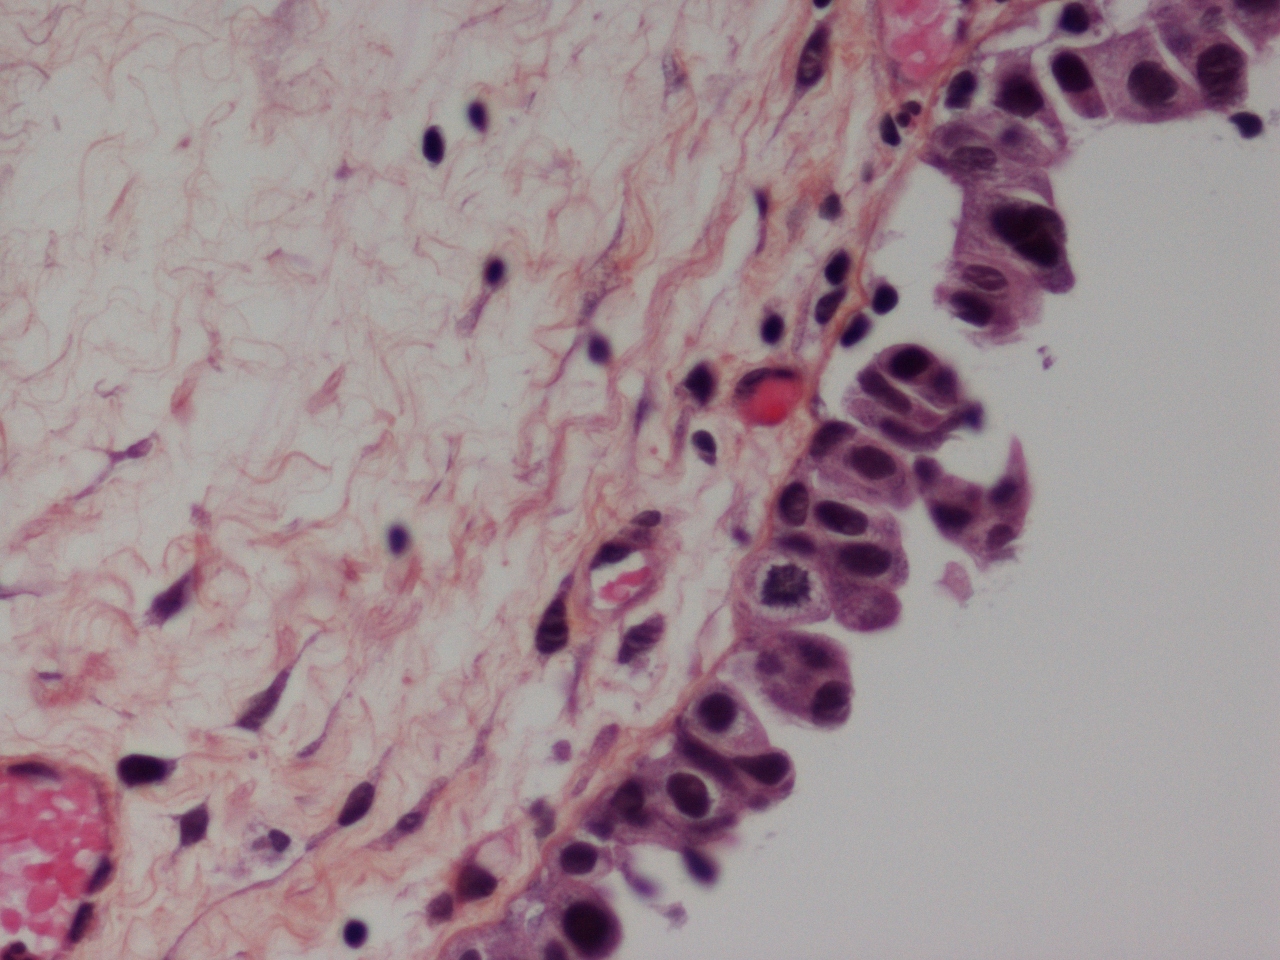

Bladder Flat Lesions

Case ID: 305